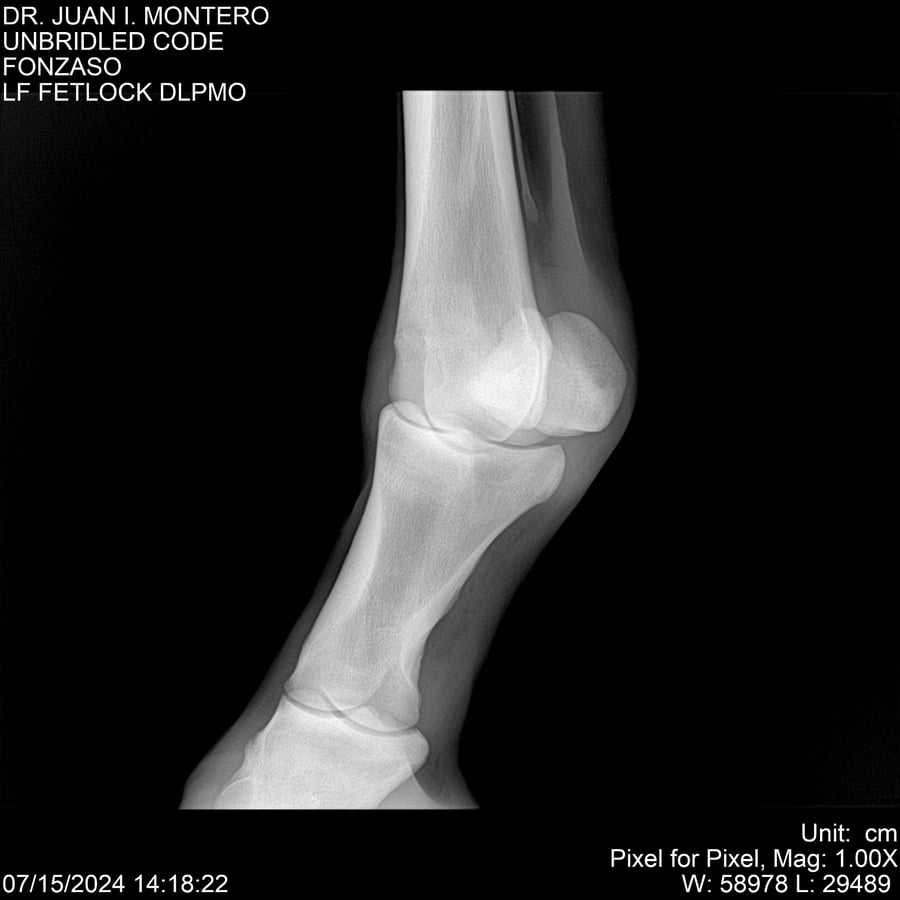

• Empresa: Abelenda N. R., Walter Hugo